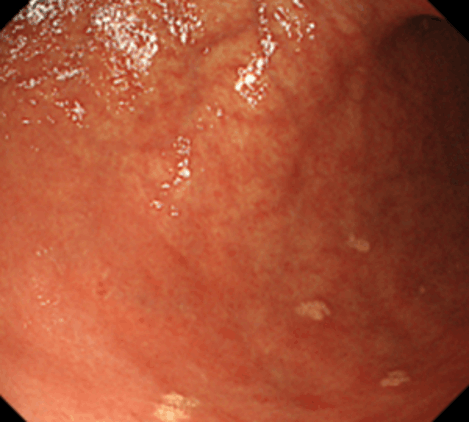

胃上皮下病変とは、胃の上皮(粘膜表層)の下の粘膜固有層(粘膜深層)や粘膜下層、固有筋層などに由来する腫瘤の総称です。以前は粘膜下層と固有筋層に局在する消化管間質腫瘍(GIST)、神経鞘腫、平滑筋腫、脂肪腫、迷入膵などを総称して粘膜下腫瘍(SMT)とすることが多かったのですが、近年は胃神経内分泌腫瘍などの、粘膜下層よりも浅層の粘膜固有層に主座を置く病変なども含めて、上皮下病変(SEL)とするのが一般的となりつつあります。本項では、従来のSMTに相当する病変について解説していきます。胃神経内分泌腫瘍については、別項をご参照ください。